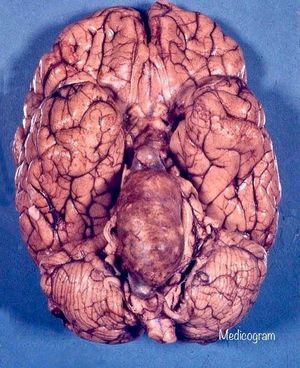

This huge aneurysm of the basilar artery is not congenital, but atherosclerotic. Severe atherosclerosis (deposition of fats in the walls of arteries) may gradually weaken the wall of an artery, promoting their aneurysm. The most common example is the abdominal aorta. The aneurysm was not broken and was found at autopsy. It caused noticeable deformation of the anterior surface of the brainstem. The aneurysm was filled with mixed thrombus arranged in several concentric layers.However, there was a light and maintaining blood flow (otherwise there would have been massive brainstem infarction, incompatible with life). Intracranial atherosclerotic aneurysms are much rarer than congenital aneurysms.